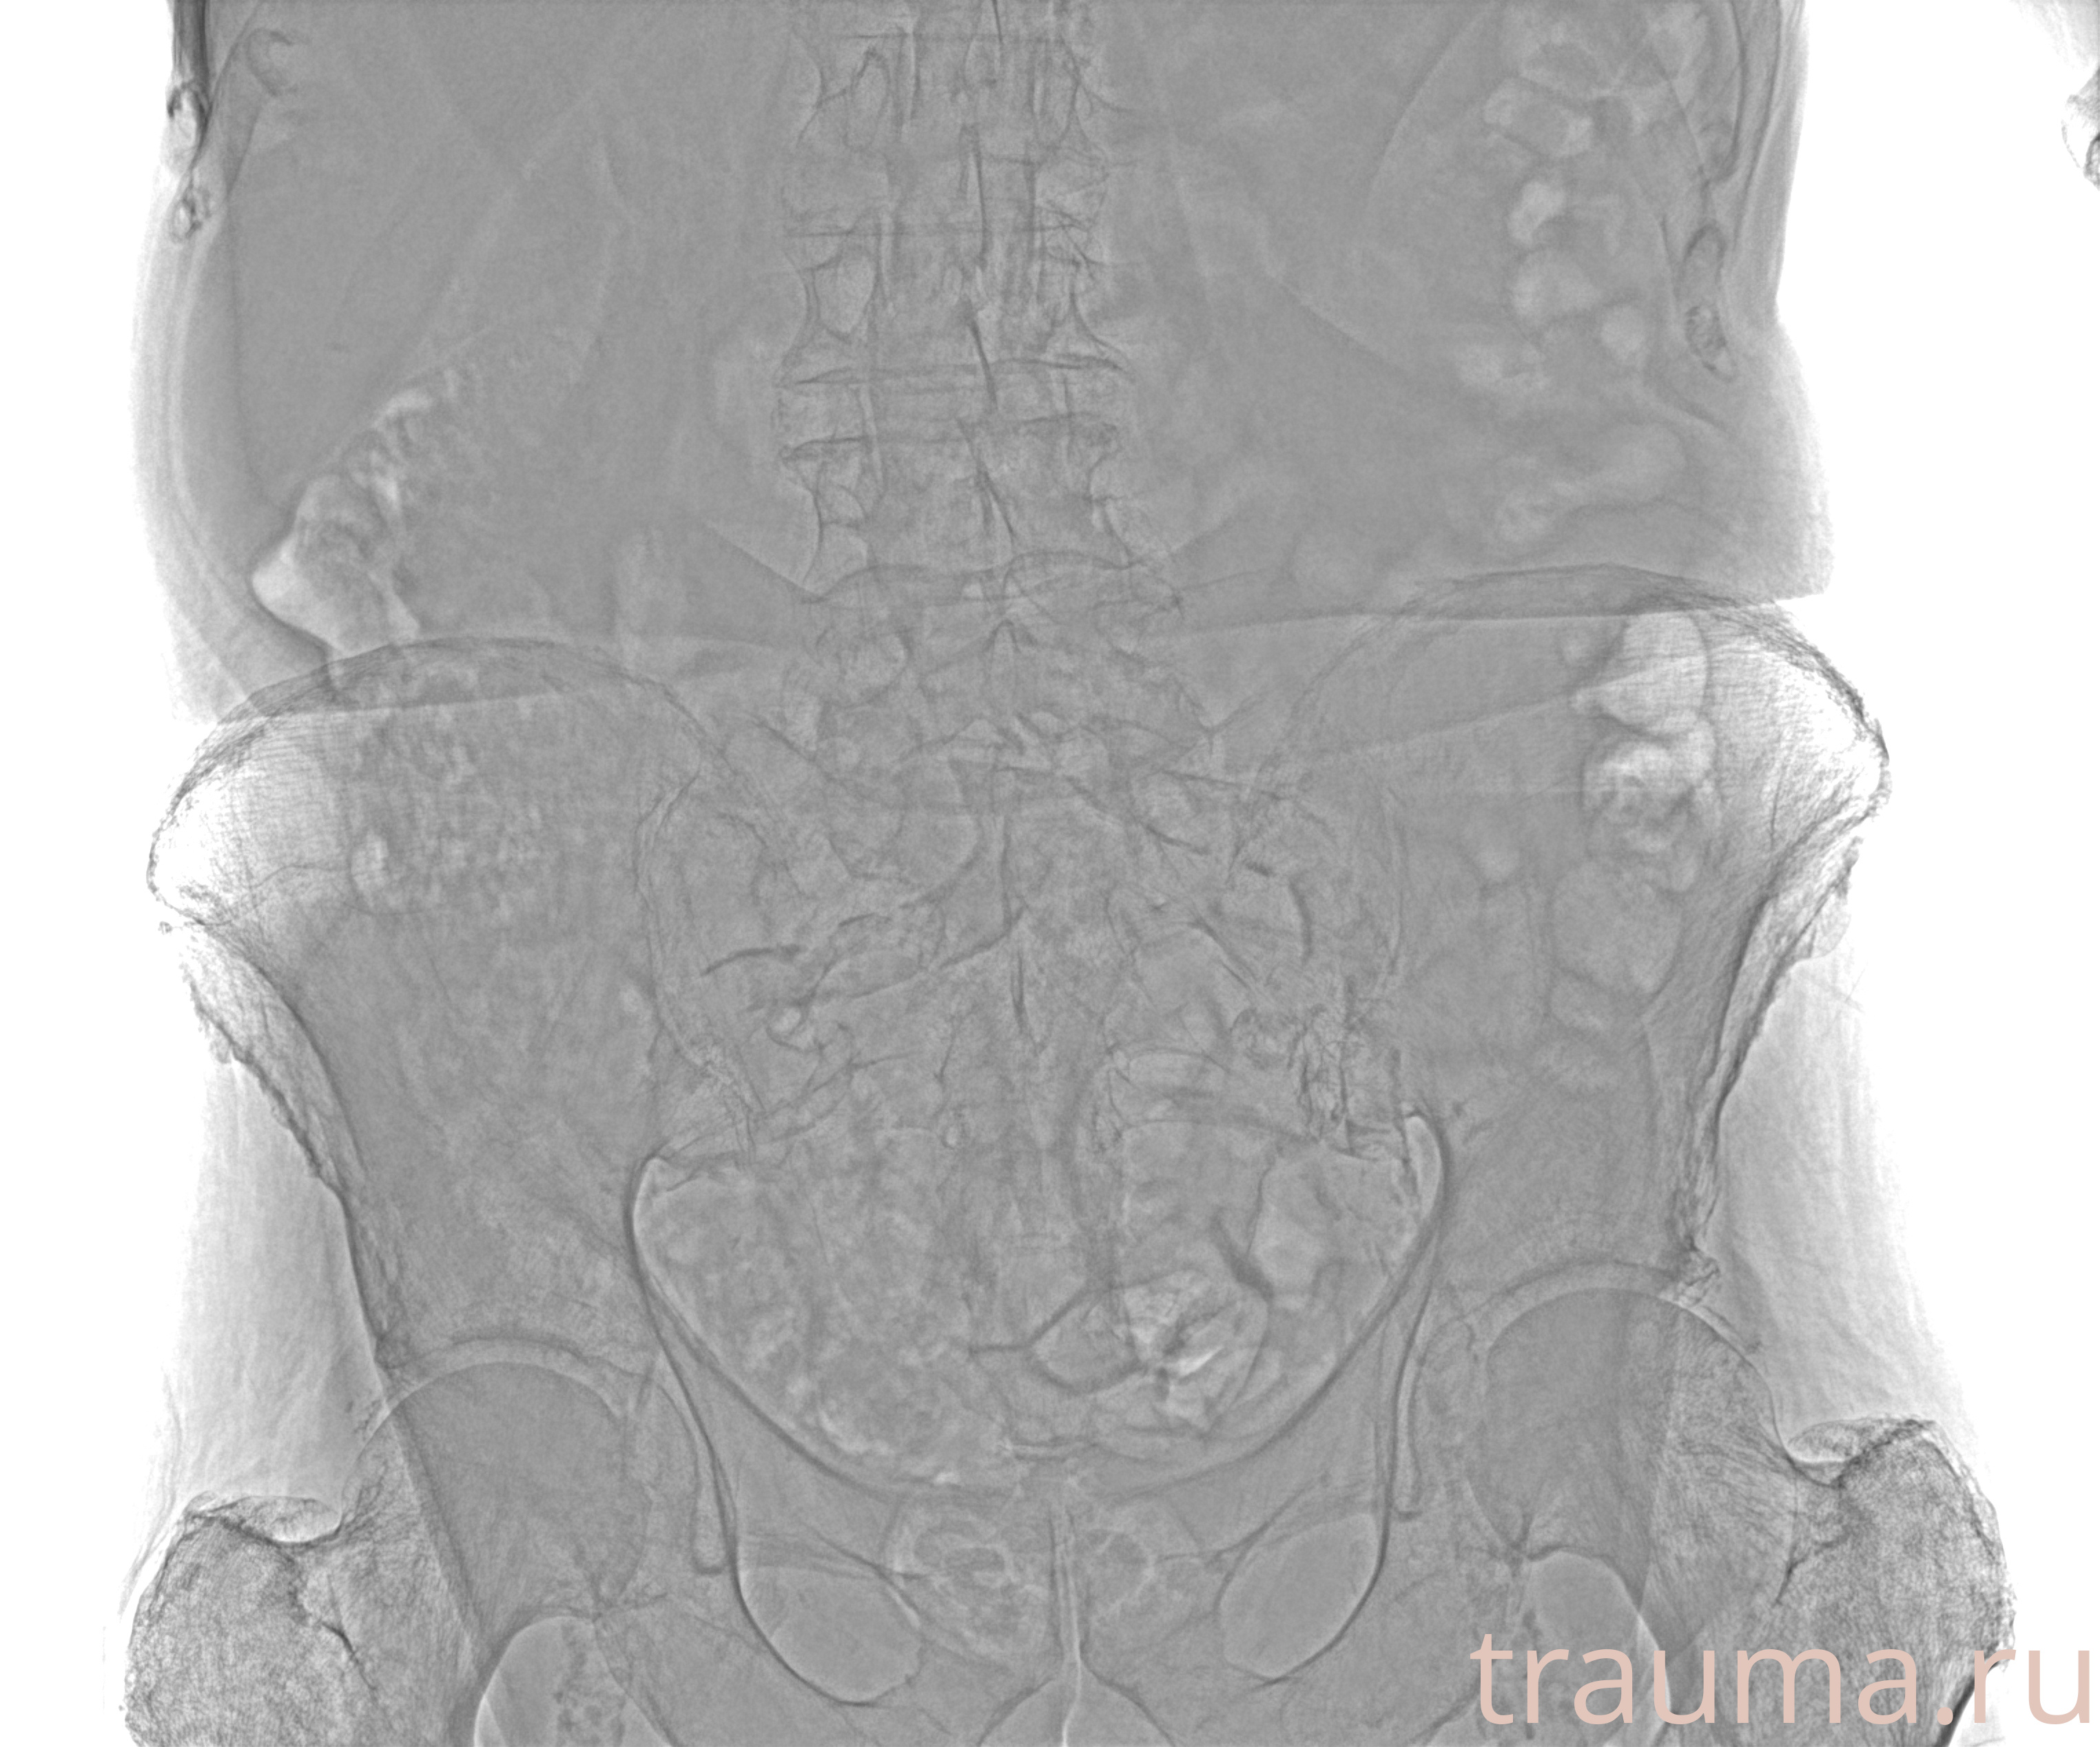

Рентген на дому: по вашему адресу приезжает врач-рентгенолог, травматолог-ортопед с мобильным рентгеновским аппаратом, проводит диагностику травмы или заболевания, делает необходимые рентгенограммы, дает рекомендации по дальнейшему лечению. Получить качественные снимки в домашних условиях возможно благодаря уникальной методике, разработанной МосРентген Центром для института  Склифосовского